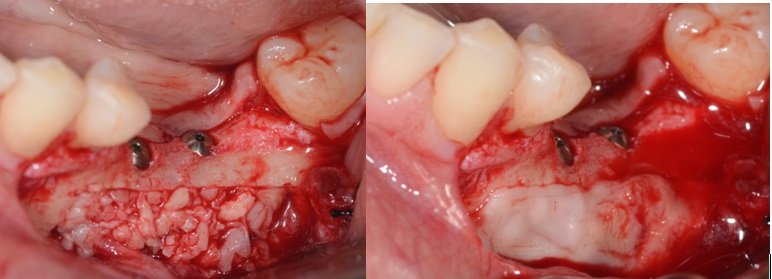

Colocação de PRF (Plasma Rico em Fibrina) sobre o nervo alveolar, desta forma, a sensibilidade do nervo volta com maior rapidez.

Preenchimento da cavidade com HA e PRF.